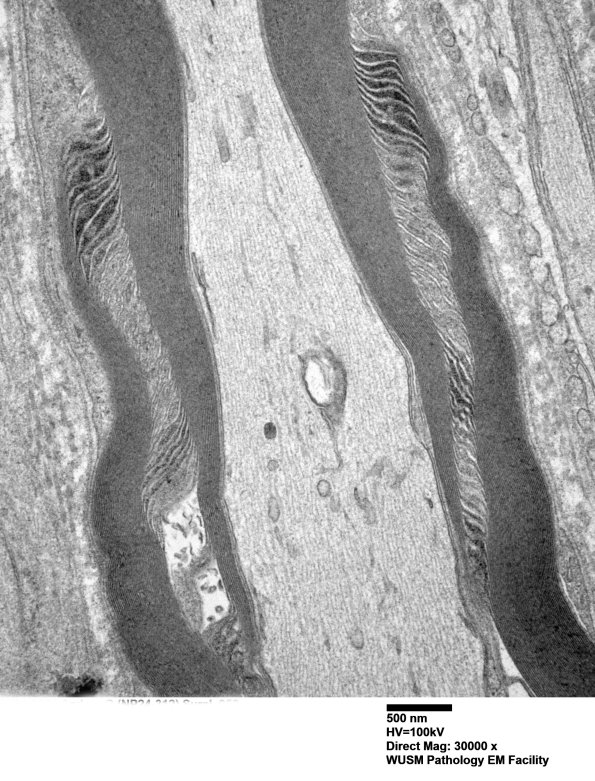

Washington University Experience | PERIPHERAL NEUROPATHY | 3 NORMAL MYELIN & SCHWANN CELLS | 3 Schmidt-Lanterman Clefts | 2A3 W24-3671 Anders G (Case 2) Sural_058 - Copy

Higher magnification of image #2A2. (electron micrograph)